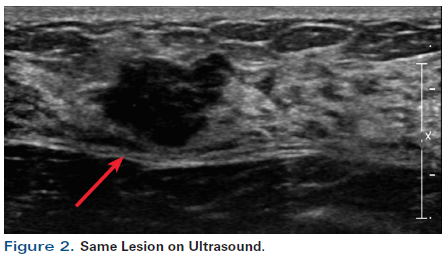

Figure 2. Same Lesion on Ultrasound.

A 55-year-old perimenopausal woman presented with a palpable lump in her left breast. Diagnostic mammogram showed a 1.8-cm spiculated mass with scattered microcalcifications within the mass (Figure 1). Comparison with her most recent prior mammogram (about 9 months earlier) showed this to be a new mass. Ultrasound confirmed a hypoechoic mass of about 1.4 cm at the 2 o’ clock position in the left breast, 4 cm from the nipple (Figure 2). Axillary nodes appeared normal anatomically. A core biopsy was obtained, which demonstrated poorly differentiated invasive ductal carcinoma of at least 0.8 cm, associated with poorly differentiated ductal carcinoma in situ (DCIS). Estrogen receptor was 1+ in 1% (negative), progesterone receptor was negative, and human epidermal growth factor receptor 2 (HER2) was 0 by immunohistochemistry. A biopsy clip was placed. A magnetic resonance imaging (MRI) scan of both breasts was obtained at an outside institution (Figure 3). This showed no additional lesions; however, the tumor area seen on MRI was estimated at 2.5 cm. A 4-mm ipsilateral internal mammary node was noted (Figure 4). The axilla seemed normal. The patient had no family history of cancer but did have a history of hypertension. She stated that she had been advised to have a bilateral mastectomy.